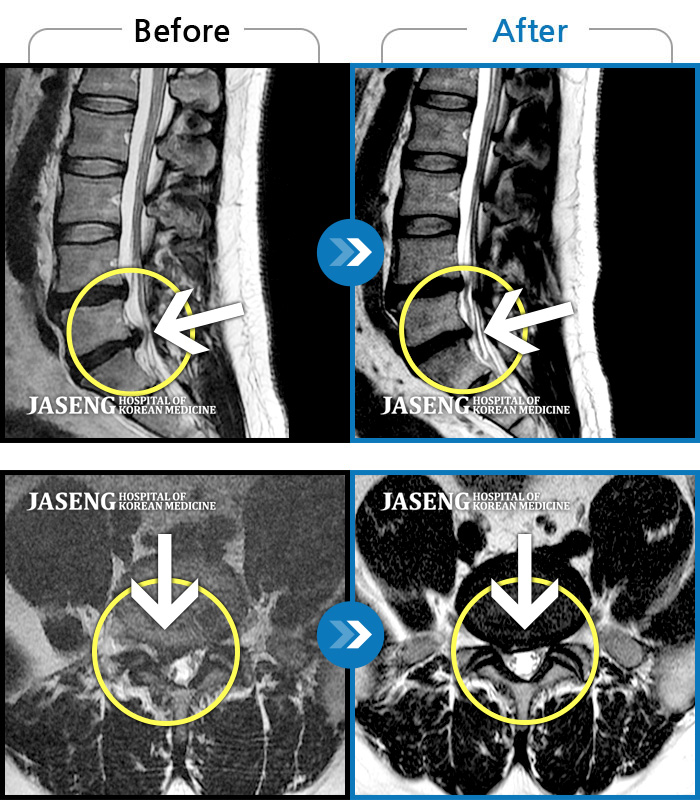

[뱸] 19.11.28~25.05.06

ȯںп Ǹ ǿ ԿǾ, ο ġ ۿ Ƿ ġḦ Ͻñ ٶϴ.